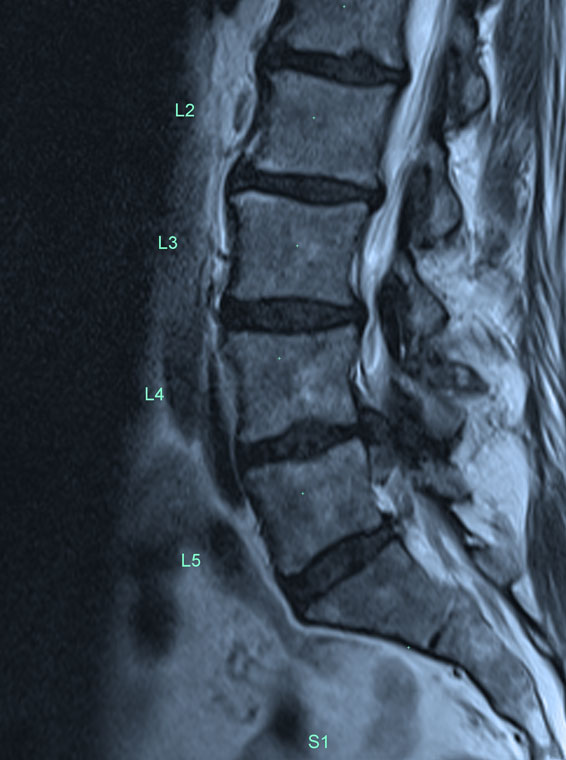

Indications for spinal fusion surgery are several. In those patients with an unstable spine where one vertebra is moving too much on another, or where there is scoliosis of the spine which is progressive, fusion surgery is used to correct the deformity as well as stabilise the spine.

In some instances axial neck or lower back pain can be managed with spinal fusion surgery. Most spinal fusion surgery is performed to protect the spinal cord or nerves from irritation or compression that can result in permanent damage to the nerves. In the situation where neck pain or lower back pain is being treated, the results of spinal surgery can be less predictable as the spinal structure is quite complicated and pain symptoms can emanate from multiple locations. Therefore this surgery for neck or lower back pain is in general, less predictable than spinal fusion surgery for spinal cord or nerve impingement, or spinal surgery which is used to treat an unstable spine as mentioned above.

Fusion of one vertebra to another using bone graft usually takes a number of months to achieve as healing is slow. The screws and rods help to stabilise the spine in this period. Once the fusion has occurred the screws and rods may still help share some of the load across the spine but with a solid spinal fusion there is usually no further movement.